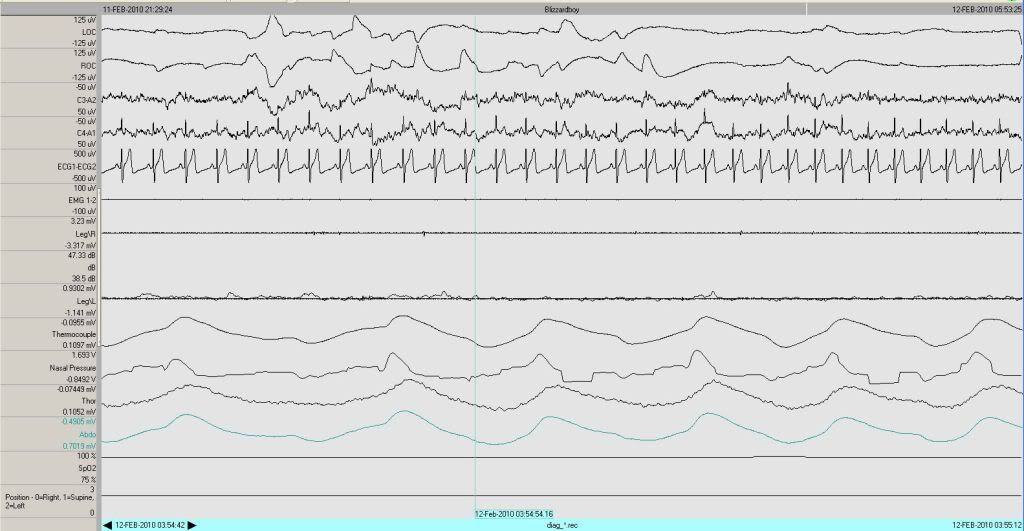

And you can't count that one, cause it's only 7.6 seconds long:

Image

Right before the limb movement... does that constitute a 90% amplitude reduction for at least 10 seconds on the thermocouple line? Nasal pressure is pretty flat for an extended period in that segment as well.

-SWS wrote:Right before the limb movement... does that constitute a 90% amplitude reduction for at least 10 seconds on the thermocouple line? Nasal pressure is pretty flat for an extended period in that segment as well.

Right. That one (in 60-second view):

and the one I had marked are the only ones I believe qualify for discussion (HOLD THAT THOUGHT!) as obstructive apneas. The other events are either central, too short or hypopneas.